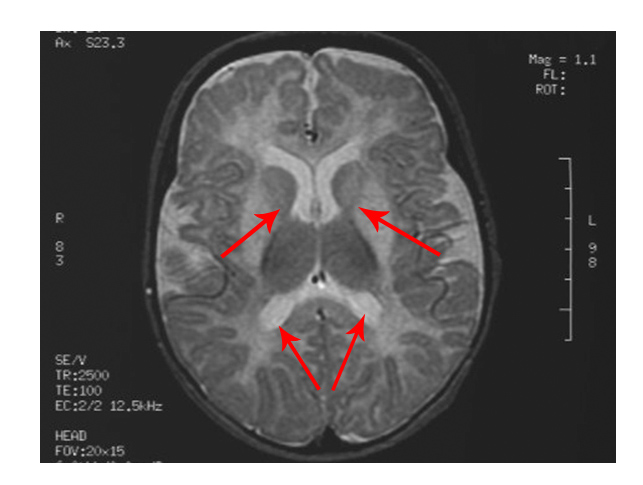

- Changes are observed in the grey matter and white matter areas in the brain

The scan shows changes in white matter within the brain as well as symmetrical abnormalities in signals (white areas) in the area known as the putamen (bottom arrows), in both hemispheres